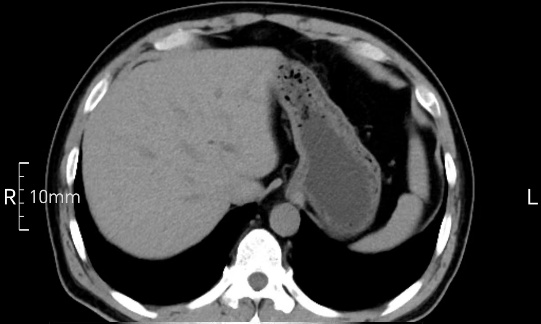

看看下面三幅便知遵醫(yī)囑的重要性。

完美禁食且喝飽飽,胃壁完美展現(xiàn)。

CT檢查前的“禁食”和“喝飽”,看似矛盾,實(shí)則合情合理,分工合作:空腹:是為了讓上腹部(肝膽胰脾腎等)的圖像清晰無干擾,并保障檢查安全。喝水:有效的充盈胃部和、腸道使圖像清晰呈現(xiàn)。兩者巧妙配合,都是為了給您一個最精準(zhǔn)的診斷結(jié)果。